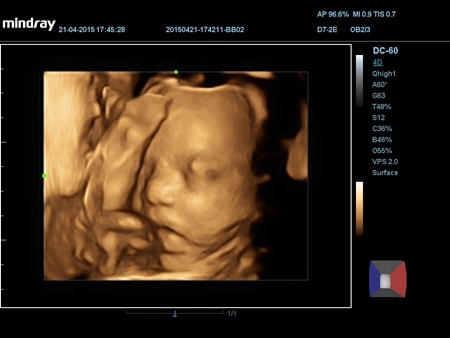

• 4D - блок объемного сканирования в реальном времени.

• 4D - блок объемного сканирования в реальном времени

• Конвексный 4D датчик Mindray D7-2E